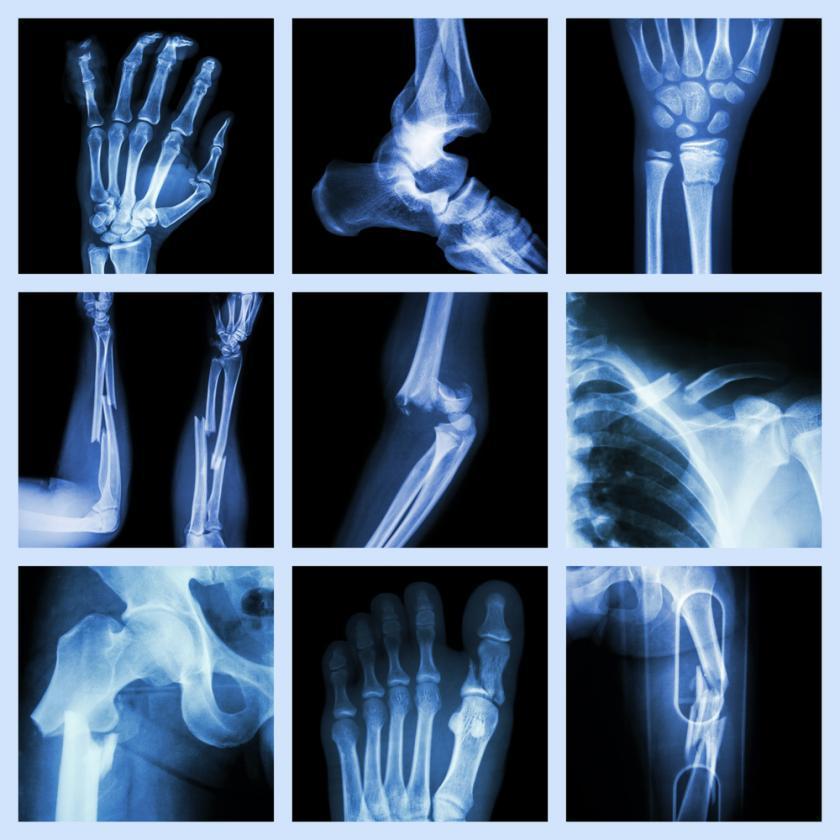

Frattura ossea

- Descrizione: Qualsiasi rottura del tessuto osseo.